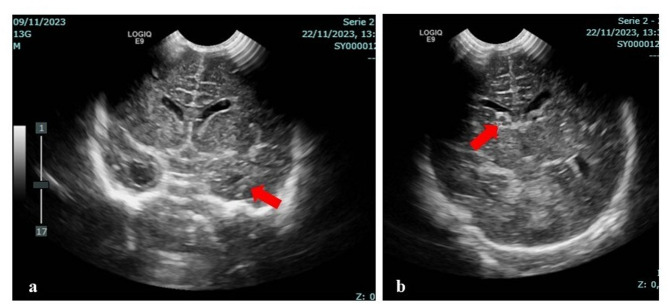

Case presentation: We report on a male term newborn showing in the first days of life hyperexcitability, tremors and increased muscular tone, in addition to thrombocytopenia, initially related to an early-onset sepsis. Obstetric history revealed that the mother underwent steroid treatment during the whole first trimester of pregnancy. She had positive CMV IgG and negative CMV IgM antibodies throughout gestation. At 15 days of age, due to the persistence of neurological and hematological signs and abnormalities found on brain ultrasound (bilateral ventriculomegaly, and an anechoic lesion within the right caudothalamic grove at first related with grade I intraventricular hemorrhage) a brain magnetic resonance imaging (MRI) was performed, showing significant lesions highly suggestive of cCMV. Although such diagnostic hypothesis was unsuspected (in light of the association of clinical manifestations with perinatal sepsis and the misleading maternal serology), however CMV DNA detection on blood and urine was carried out, giving positive results in both samples for connatal infection diagnosis. Newborn CMV IgG and IgM antibodies resulted positive, while the IgG avidity test showed high values according to a likely early intrauterine infection. The antiviral therapy was therefore begun and continued for 6 months. He currently is 6 months old and included in a multidisciplinary follow-up. His growth is within the normal limits, but a neuromotor delay is present. Audiological and ophthalmological evaluations, laboratory as well as multiorgan ultrasound (US) examinations have not revealed further anomalies to date.